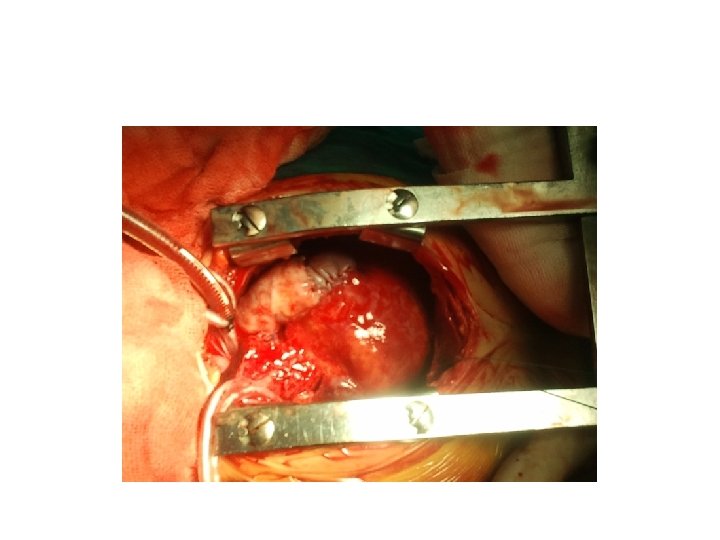

Ne yapılabilir • Kapalı kalp cerrahisi • Pda ligasyonu, shunt operasyonları, banding, • Açık

Ne yapılabilir • Kapalı kalp cerrahisi • Pda ligasyonu, shunt operasyonları, banding, • Açık kalp cerrahisi • Pompa kullanıldığı durumlar